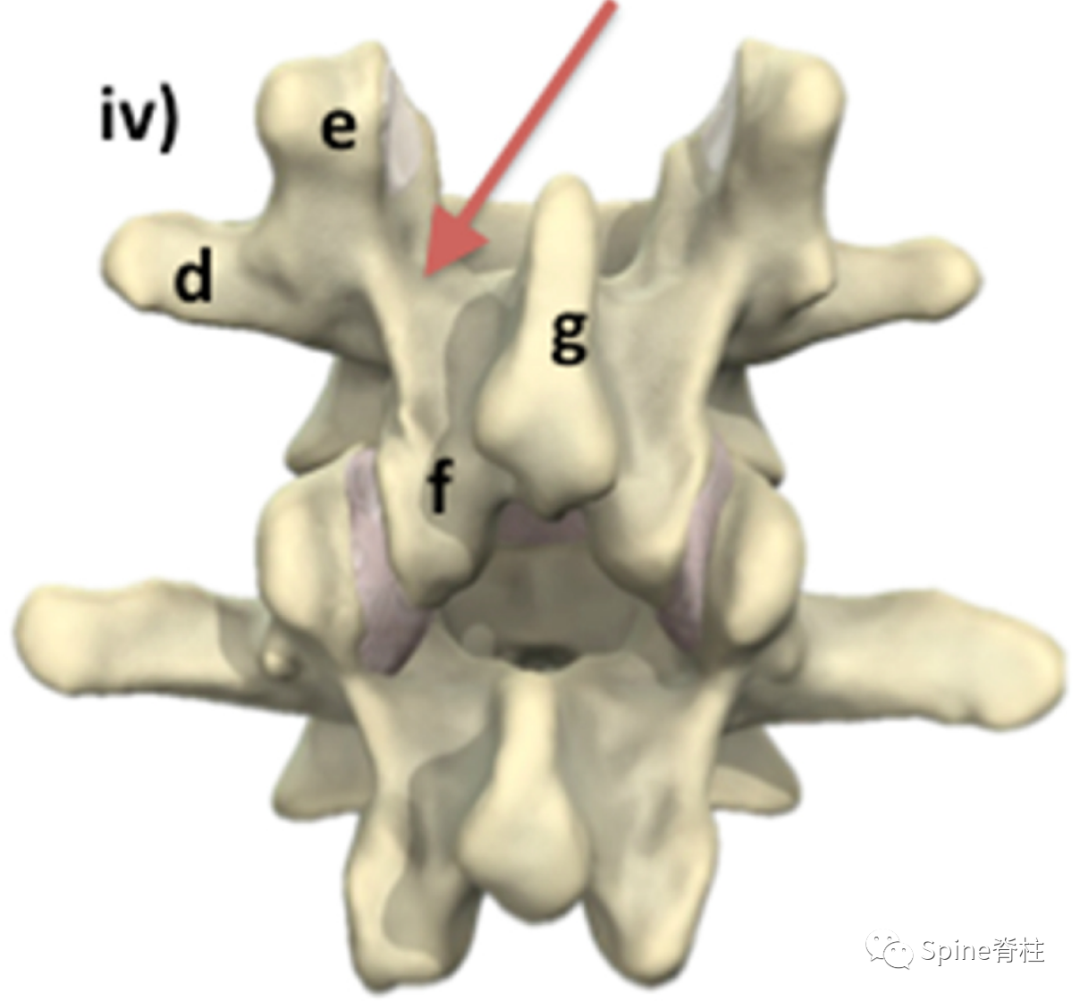

有研究发现磁共振上椎弓根出现T2高信号改变是青少年和儿童峡部裂的早期诊断征象。同时,存在椎弓根高信号改变也是保守治疗后能达到骨性愈合的良好预测指标(也就是说存在T2椎弓根右高信号改变的峡部裂患者,其峡部裂经保守治疗愈合的可能性大)

右上图为椎弓根高信号改变(+),右下图为(-)

左侧为椎弓根水肿阳性,右侧为椎弓根水肿阴性,有研究发现峡部裂伴随着椎弓根水肿,支具固定愈合率更高

左侧早期峡部裂伴椎弓根水肿,支具固定6月后愈合

Sairyo教授研究发现磁共振上椎弓根出现T2高信号改变是青少年和儿童峡部裂的早期诊断征象。同时,存在椎弓根高信号改变也是保守治疗后能达到骨性愈合的良好预测指标(也就是说存在T2椎弓根右高信号改变的峡部裂患者,其峡部裂经保守治疗愈合的可能性大)。

图:右上图为椎弓根高信号改变(+),右下图为(-)